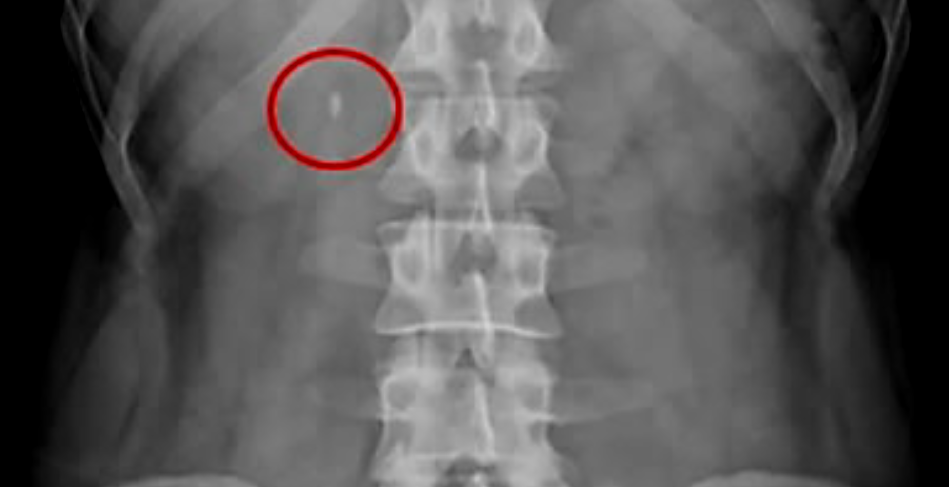

요로결석 치료는 우선 진단을 한 후에 치료방법을 결정하게 되는데요. 진단은 옆구리 통증의 확인, 소변검사, 신장요관과 방광 부위를 촬영하는 검사, 신장, 요관, 방광의 모양과 기능을 동시에 보면서 진단, 엑스레이로 확인되지 않는 요석의 위치 확인을 위한 초음파 검사, CT촬영을 통해서 요로결석 진단을 하게 됩니다.